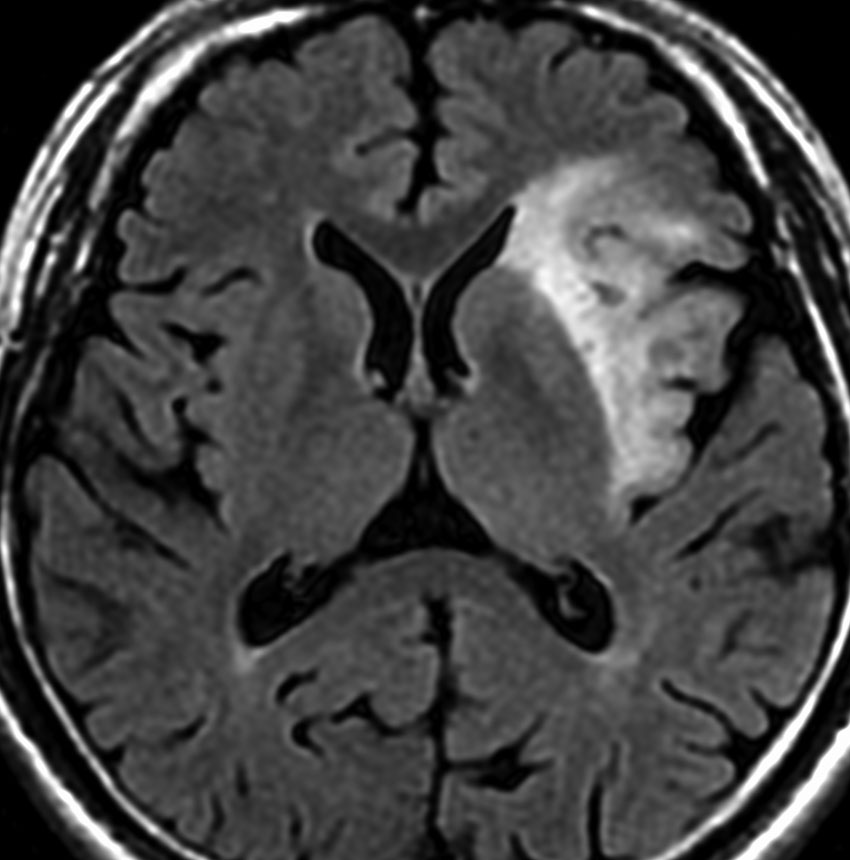

若い女性の左前頭葉から島回,側頭葉を侵す腫瘍で,てんかん発作で発症し,開頭生検 biopsy しました。

一部で,細胞密度が高く,核の腫大とクロマチンの増量,核間距離の短縮があり,核分裂像が認められ,MIB-1染色率が10%です。組織学的には退形成性乏突起膠腫グレード3とされました。

IDH変異あり,1P/19q欠失あり,ATRX変異なしです。

乏突起膠細胞系グリオーマなので,放射線治療の高線量領域はあまり広くとりません。

IMRT Simultaneous Integrated Boost (SIB)で,FLAIR高信号の領域に54グレイ27分割,周囲仮定浸潤領域 generous local areaに46グレイを照射しました。

テモゾロマイド75mg/m2を併用しています。

左の画像は放射線治療直後のMRIですが,すでに腫瘍の縮小がみられます。

テモゾロマイドの維持療法は,24コース 2年間行い,それ以降は無治療としました。

照射後7年の画像です。腫瘍は縮小したまま,患者さんは無症状で経過しています。